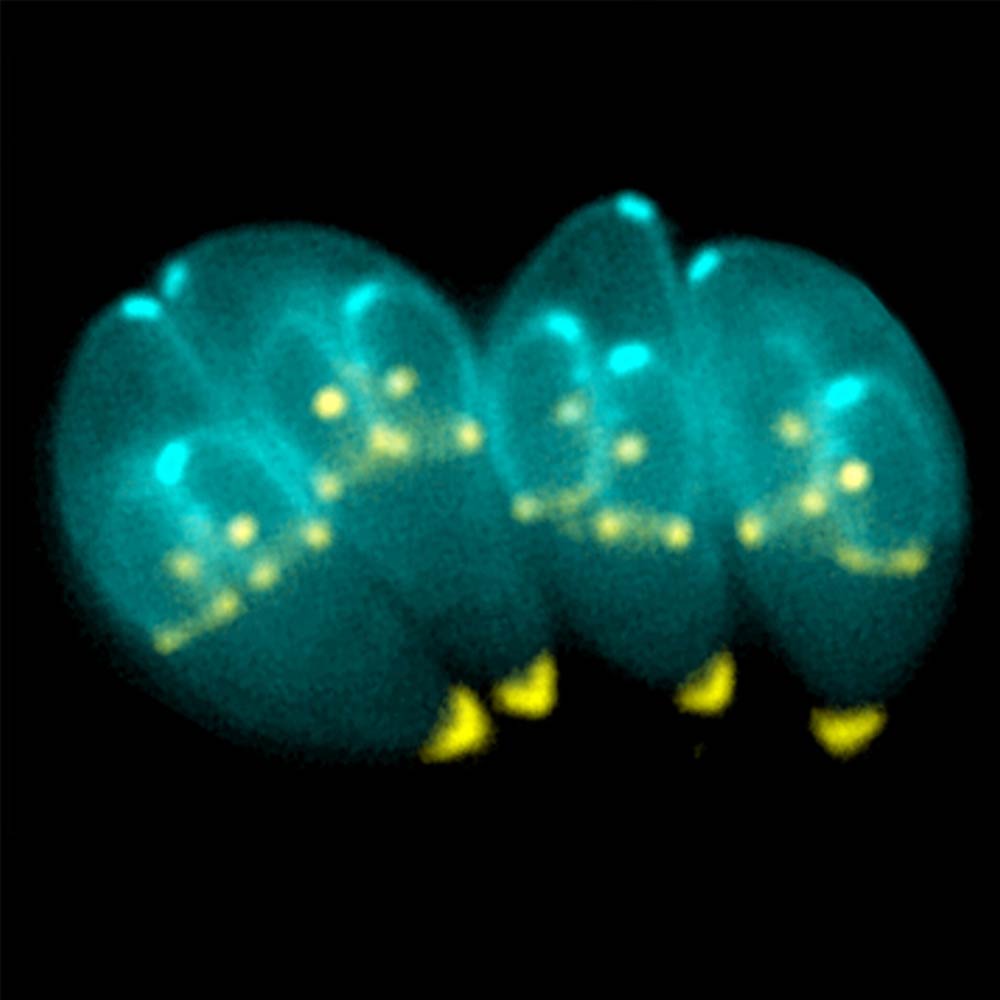

Für eine präzise Diagnose stehen uns in der tierärztlichen Augenheilkunde spezielle Instrumente und Verfahren zur Verfügung. Dazu gehören die Spaltlampenuntersuchung zur detaillierten Betrachtung der vorderen Augenabschnitte, die Ophthalmoskopie zur Beurteilung des Augenhintergrunds (Netzhaut, Sehnerv), die Tonometrie zur Messung des Augeninnendrucks (wichtig bei Glaukomverdacht) sowie Ultraschalluntersuchungen des Augapfels und der Augenhöhle. Bei Bedarf können auch weiterführende Tests wie zytologische Untersuchungen von Abstrichen oder Gewebeproben (Biopsien) durchgeführt werden.

Das Spektrum der behandelten Erkrankungen ist breit und umfasst unter anderem Lidfehlstellungen (z.B. Entropium, Ektropium), Hornhautverletzungen und -geschwüre, den Grauen Star (Katarakt), den Grünen Star (Glaukom), Entzündungen im Augeninneren (Uveitis) sowie Netzhauterkrankungen. Die Therapieansätze reichen von medikamentösen Behandlungen mit speziellen Augentropfen oder -salben bis hin zu komplexen mikrochirurgischen Eingriffen, um das Sehvermögen bestmöglich zu erhalten oder wiederherzustellen und Schmerzfreiheit zu gewährleisten.